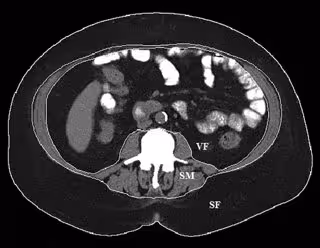

Para obtener más información, el doctor Takahashi y sus colegas estudiaron las tomografías computarizadas de 16 pacientes con sobrepeso u obesos que se habían sometido a una embolización de la arteria gástrica para tratar el sangrado gastrointestinal. Las tomografías computarizadas, cuando se usan junto con un software especial, permiten mediciones de la composición corporal en función de las diferentes densidades de tejidos, como la grasa y los músculos.

Se realizaron exploraciones antes y aproximadamente 1,5 meses después del procedimiento. Se compararon los resultados con los de un grupo de control de 16 pacientes ambulatorios que no se sometieron a una embolización de la arteria gástrica izquierda, pero a los que se les realizaron tomografías computarizadas en dos periodos diferentes ante la presencia de dolor abdominal no específico.